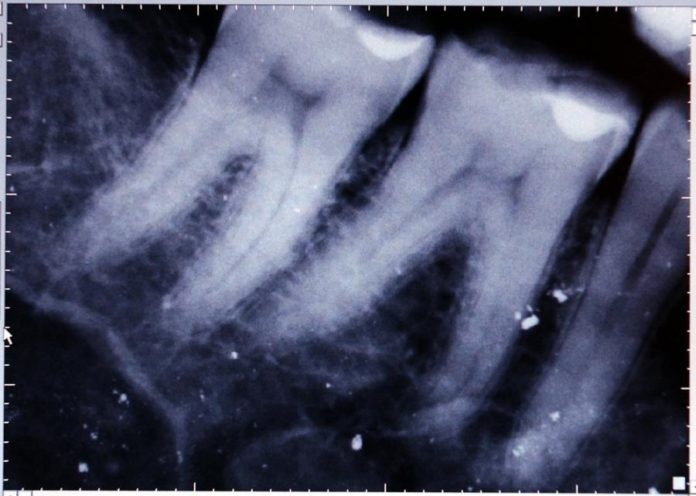

Coimbra, 14 dez 2020 (Lusa) – A Faculdade de Medicina da Universidade de Coimbra (UC) identificou uma “assinatura salivar” que abre caminho para a deteção precoce em crianças da cárie dentária, que é a doença mais prevalente naquela faixa etária, foi hoje anunciado.

O trabalho, intitulado “Perfis metabolómicos salivares na cárie dentária em idade pediátrica”, traz novas perspetivas para o diagnóstico precoce da cárie dentária em crianças, a doença mais prevalente em todo o mundo nesta faixa etária.

“A cárie dentária em idade pediátrica representa um grave problema de saúde pública, com um considerável impacto na qualidade de vida das crianças e suas famílias”, refere o comunicado, referindo que, até à data, ainda não tinha sido “identificado um preditor de risco consistente que permita a sinalização precoce de crianças de alto risco para a doença”.